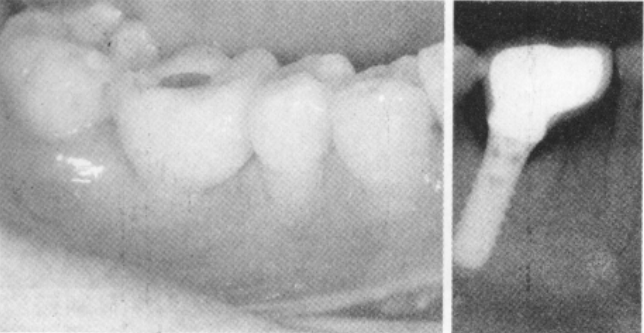

术后常规抗感染治疗。患者诉术后2d自觉术区中度肿痛不适,术后第3天明显加重,但未诉下唇区麻木不适。患者种植体植入后3个月复诊,锥形束CT检查显示种植体骨结合较好,下颌神经管内的骨折片已改建吸收消失。

接着制作种植体上部修复体,钯金烤瓷冠殆面开洞,粘接固位。种植体植入后3.5个月即完成上部修复及负重,术后电话随访2年,患者无不适。